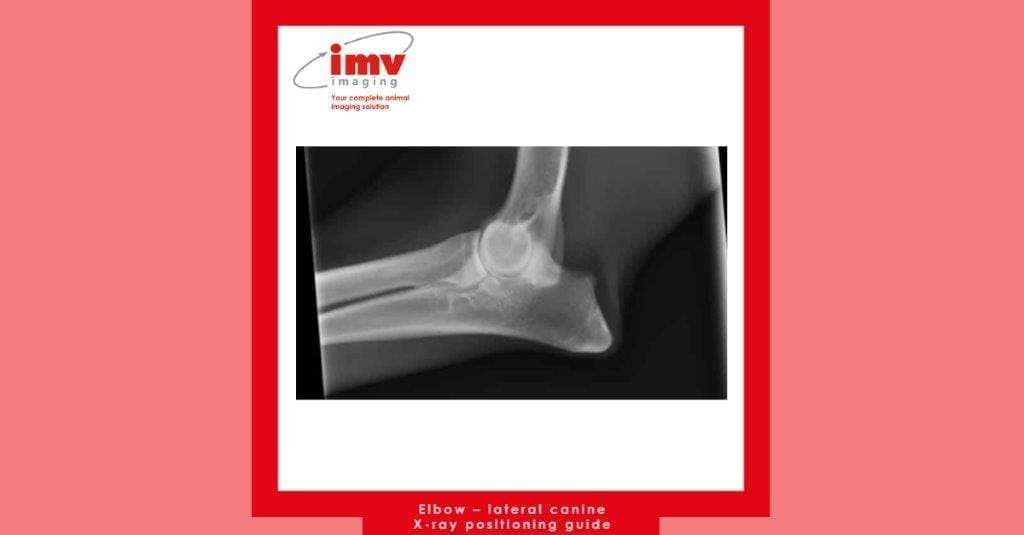

Free Download: Elbow – lateral canine x-ray positioning guide

• Position dog in lateral recumbency, lying on the side you want to X-ray

• Pull other leg back and secure

• Use cotton wool or foam pads to ensure radius and humerus are parallel to the plate

• Centre over humeral condyle and collimate to 1/3rd of the way along the radius/ulna distally and 1/3rd of the way along the humerus proximally; this can be extended further if a fracture is suspected

• Elbow should be in a neutral position, i.e. flexion of around 90°

• Ensure L/R marker is in primary beam.

• Ensure condyles are superimposed – have a feel as you position the dog, and ensure centred right over them.

• Cotton wool is great for lateral elbow positioning, as can be shaped to provide right level of support